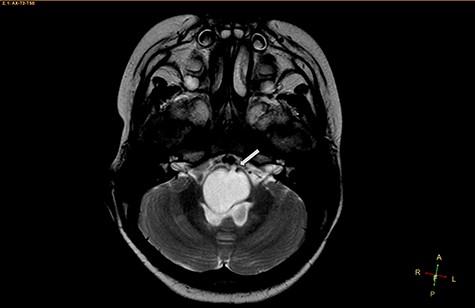

A 3-year-old male, who suffered from a sudden, tonic–clonic seizure, followed by a short period of unconsciousness, was instantly transported to Children’s Hospital 2. The patient’s medical history was normal. No neurological deficits were detected during the clinical assessment, and laboratory tests and electroencephalography were within acceptable ranges. The clinician performed a brain magnetic resonance imaging (MRI) scan, with contrast agent. No lesions were recognized in the supratentorial structures. A clear boundary cystic mass (27 × 25 × 26 mm3) was located in the medulla oblongata, without perilesional vasogenic edema. Hydrocephalus was not observed. The signal intensity of the mass was low on the sagittal T1-weighted image (Fig. 1) and high on the axial T2-weighted image (Fig. 2). On coronal fluid-attenuated inversion recovery imaging, the mass was isointense relative to the parenchyma, but the intensity was higher than that of cerebrospinal fluid (CSF, Fig. 3). On susceptibility-weighted imaging, no indicators of hemorrhage or ossification were observed within the mass. The mass was partially hyperintense on diffusion-weighted imaging (DWI) and slightly hypointense on the apparent diffusion coefficient (ADC) map. The mean ADC values of the parenchyma, mass and CSF were 0.71, 1.3 and 1.59 × 10−3 mm2/s, respectively (Fig. 4). On T1-weighted imaging, with contrast enhancement, the thin wall of the mass was very slightly enhanced, and we observed a tiny nodule inside the mass that was strongly enhanced (Fig. 5). With a provisional diagnosis of pilocytic astrocytoma, the patient underwent surgery to completely eradicate the tumor. Eventually, the histopathological result revealed a typical EC (Fig. 6). The postoperative period was uneventful, and the patient was discharged after 2 weeks.

Axial T2-weighted image, showing a hyperintense, cystic mass inside the medulla oblongata. Exceptionally, the lesion appears to progress from extra-axial to intraparenchymal (arrow).

Two widely accepted hypotheses have been suggested to explain the establishment of extra-axial and intra-axial ECs. Theoretically, ECs form due to aberrations in ectodermal residues or the sequestration of ectodermal components during an early stage of gestational growth, between the 3rd and 5th weeks. The remnants of these ectodermal cells eventually proliferate, forming an EC [3, 4]. Retrospectively, the findings shown in Fig. 2 appear to show the progression of the lesions from the extra-axial to the intraparenchymal medulla oblongata; therefore, we have contributed additional evidence to reinforce the hypothesis regarding the primitively extra-axial root of EC development.